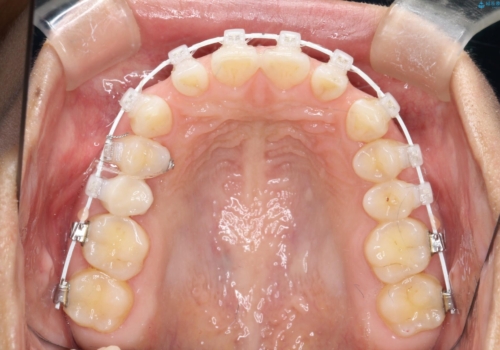

- 矯正装置

- 審美装置

- 歯と歯の間に隙間があることを主訴に来院されました。

短期間での治療終了を希望され、ワイヤー矯正にて治療を行い1年ほどで治療を終了しております。

下顎前歯は矯正後補綴治療を行なっております。